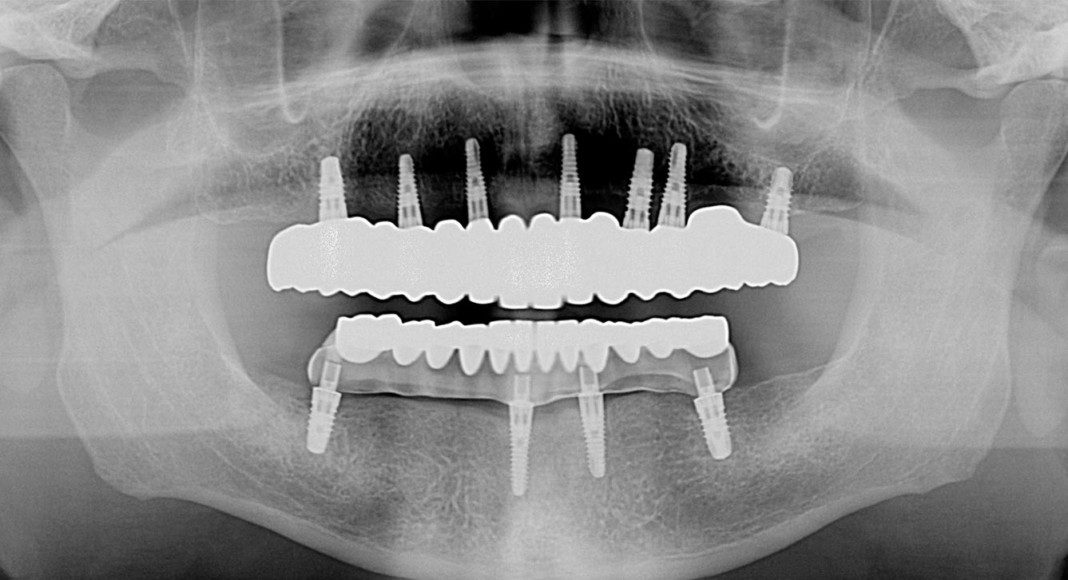

The panoramic x-ray before treatment. Note his excellent bone. Bone is precious and should not be removed (like the All-on-4 protocol).